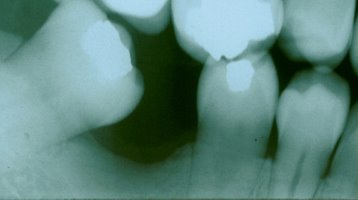

Orthodontics To Upright A Severely Tilted Molar

This patient had lost his first molar and the molar behind it collapsed

into the residual space. This was not a situation that was conducive to

placing a fixed bridge because of the misalignment. By performing a

simple, minor orthodontic procedure, the tooth was uprighted into its

original position and replaced with a beautiful fixed bridge. Now this

patient is able to chew his food properly, and lessen his chances of TMJ

(jaw joint) problems. |